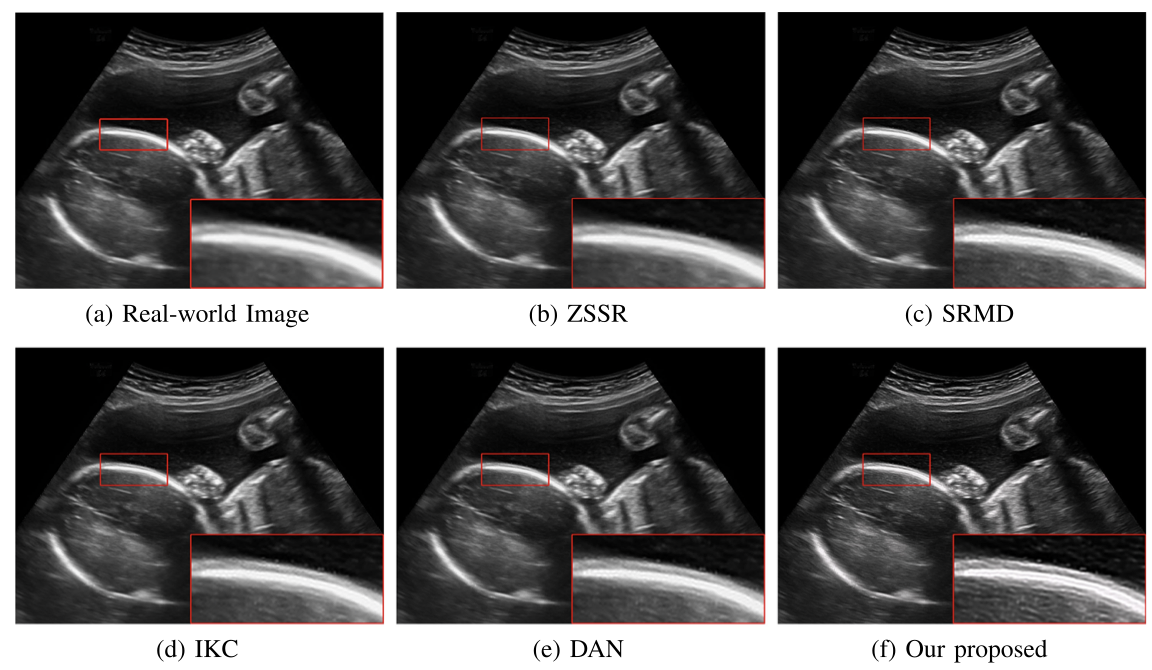

对于超声临床诊断而言,超声影像超分辨(ultrasound image super-resolution)可以提高超声成像质量,从而提高疾病诊断的准确性。但由于传感设备和传输介质的差异,实际场景中超声成像其退化模糊过程是未知且不可控的。为了解决未知退化场景超声医学影像准确超分辨的难题,团队提出了一种有效的基于退化模糊自估计且结合渐进残差学习和记忆提升机制的超声影像盲超分方法,初步实现了真实场景超声影像准确超分辨。相关研究成果发表在人工智能、计算机医学信息交叉领域一区TOP期刊《IEEE Journal of Biomedical and Health Informatics》(IF: 7.7)。公司为论文第一完成单位,太阳集团tyc4633刘恒教授、硕士生刘建勇分别为论文第一、第二作者。

(真实场景超声影像盲超分效果对比图)